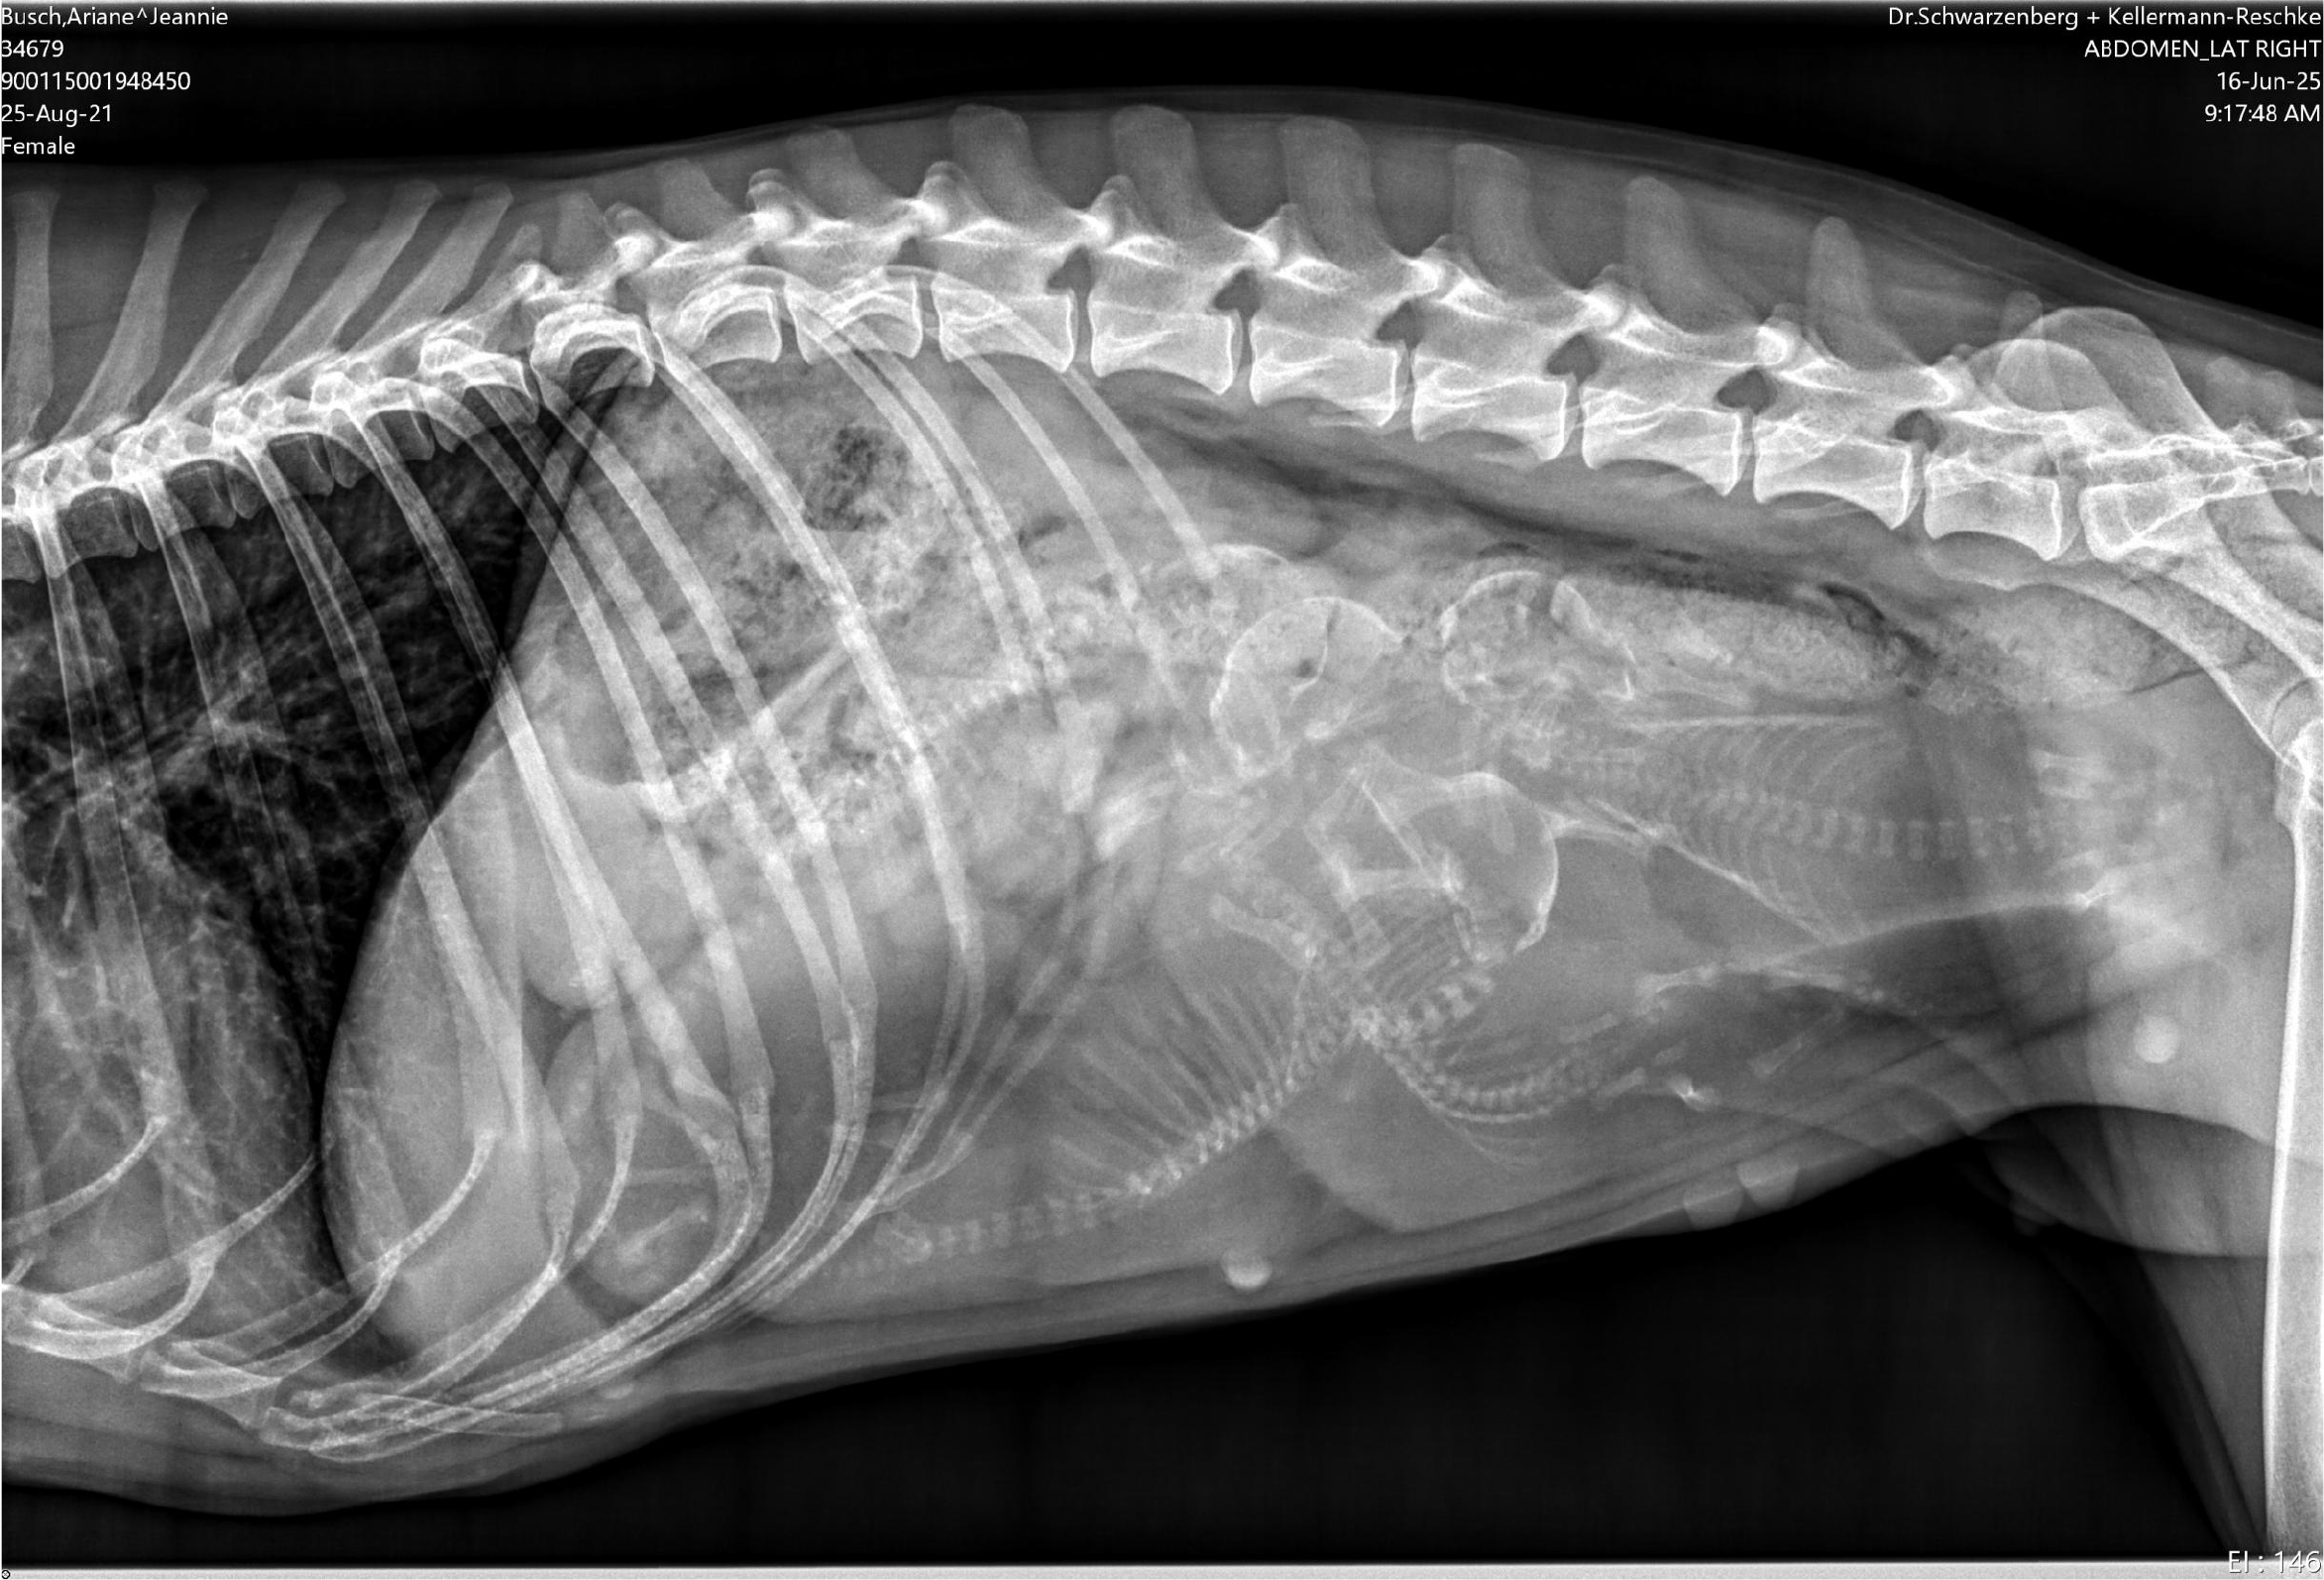

Unsere bezaubernde Jeannie „Tova‘s Riesling Surprise in Germany“ wurde Ende April von unserem charmanten Mio „Golden Nugget's Achilles“ gedeckt.

Wir erhoffen uns von dieser Verpaarung von zwei F3 Windsprites eine Erhöhung der genetischen Diversität mit den damit verbundenen positiven Auswirkungen auf die langfristige Gesundheit der Rasse. Apropos Gesundheit: Jeannie und Mio sind bereits 3,5 und 5,5 Jahre alt. Bis zur Zulassung der F3 Silken Windsprites hat es ja bekanntlich einige Jahre gedauert. Positiv daran ist, dass wir wissen, dass beide Hunde eine phantastische Konstitution und Gesundheit haben. Beide sind körperlich total fit und wirklich robust und unempfindlich – eigentlich waren sie noch nie richtig krank und vertragen jedes Futter.